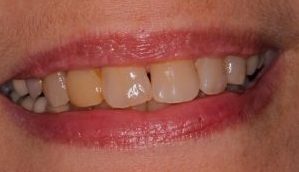

Candidates for dental implants can expect a high success rate with the procedure, with results lasting as long as a lifetime. Because each implant and artificial tooth is personalized to your needs, they will look and feel just like your natural teeth.

If you are considering dental implants in Bristol, Wolcott, Plantsville or nearby, our team will help keep you informed about what to expect about our dental implant process.